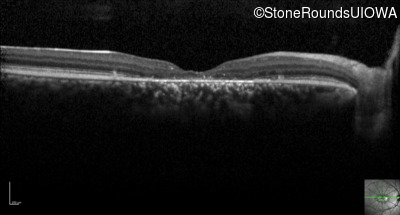

Optical Coherence Tomography - Right - 20/100 +1

Exemplar / OCT Stack

Optical Coherence Tomography - Right - 20/80 -1

Optical Coherence Tomography - Right - 20/100